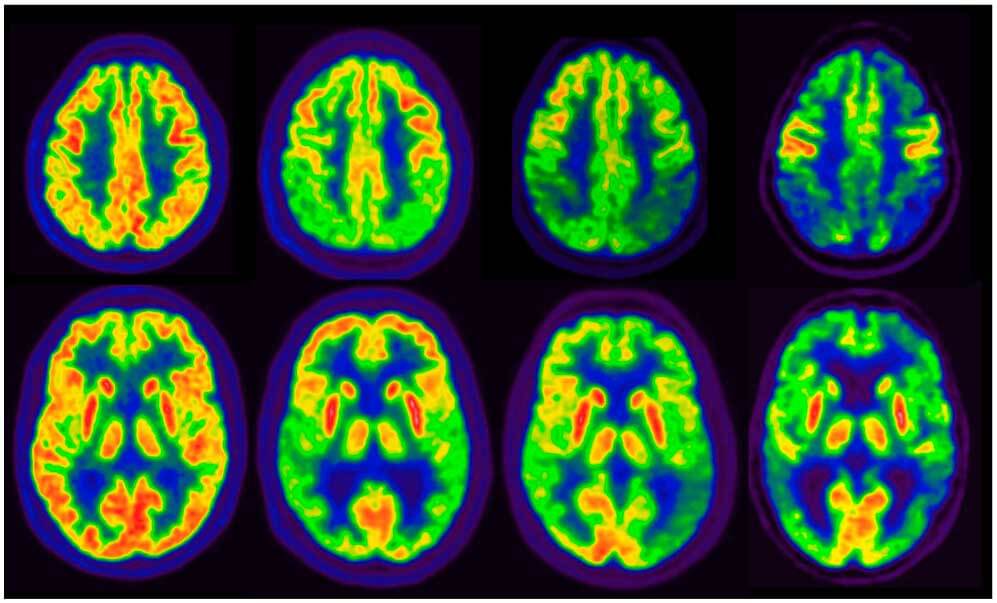

Frecuencia y resultados clínicos asociados con la positividad cerebral de tau en la tomografía por emisión de positrones

19 junio 2025

En un estudio observacional de gran tamaño se observó que la tasa de PET cerebral positivo para tau alcanzaba un 10%  en individuos sin deterioro cognitivo, y la combinación de positividad para PET de amiloide beta (Aβ) y tau se asoció con un alto riesgo de progresión clínica, tanto en la etapa preclínica como en la sintomática de la enfermedad de Alzheimer. Estos hallazgos subrayan el potencial de la PET para tau como biomarcador para la estadificación de la enfermedad. JAMA, 16 de junio de 2025.